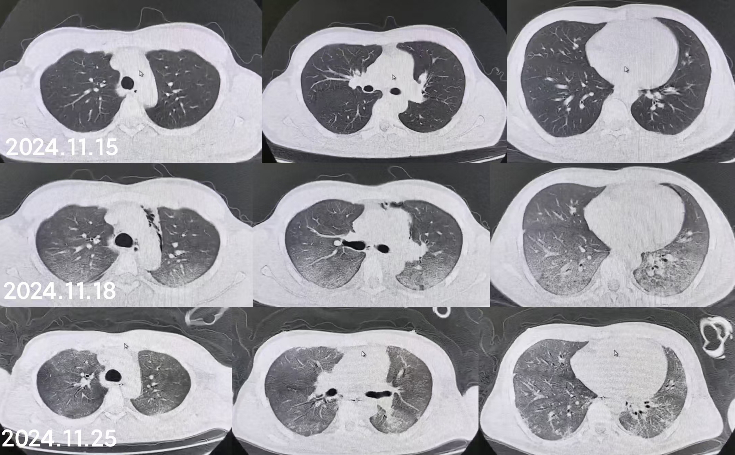

1 病例资料2024-11-15,某工地操作间有值班人员3人,分别为上铺(距地面1.8 m)A某,下铺(距地面0.4 m)B某、C某,事发当天为午休时间,设备出现故障,下午14时维修人员D某进入操作间维修,并将门窗打开,完成维修操作;事发后24 h内4名患者均出现不同程度的恶心、呕吐等消化道症状,起初考虑可能与食物中毒有关,前往当地医院就诊,完善血便常规、胸腹CT等相关检查未见明显异常,在医院给予吸氧补液静卧留观,留观期间4人先后出现不同程度的咽痛、咳嗽、胸闷、憋气等不适,吸氧不能缓解,再次行胸部CT检查示双肺弥漫性改变,间质改变可能,考虑为吸入有毒有害气体,后经采样检测操作间气体残留为全氟-4-甲基-2戊稀[Perfluoro(4-methylpent-2-ene),D1](D1纯度99.92%),导致急性呼吸窘迫综合症(acute respiratory distress syndrome, ARDS)。参照2002年职业性急性有机氟中毒诊断标准[1],A某诊断为急性中度有机氟气体中毒,B某、C某、D某诊断为急性重度有机氟气体中毒(PaO2/FiO2 < 100 mmHg,1 mmHg=0.098 kPa)。立即给予大剂量(120 mg)甲泼尼龙琥珀酸钠治疗,同时补充多种微量元素,加用甲钴胺、硫辛酸,钙剂解毒,后续加用特殊解毒剂乙酰胺治疗。治疗1周后,上铺的A某胸闷、憋气症状较前好转,影像未见明显进展,但患者仍遗留有间断气短症状;其余人员病情持续恶化,出现呼吸衰竭,转入重症医学科,给予气管插管接呼吸机辅助通气,维修人员D某上呼吸机后能基本维持,但不能脱机,继续观察患者病情变化;而下铺患者B某、C某症状不断加重,即使给予呼吸机治疗低氧状态仍未见明显改善,于2024-11-29转入本院进一步治疗。B某、C某入本院时查体:双肺叩诊呈清音,双肺呼吸音粗,可闻及干湿性啰音,具体指标见表 1,图 1、2为肺部影像进展情况。入院给予镇静镇痛、机械通气及抗感染、抗炎、抑酸等治疗,呼吸困难仍持续加重,存在难以纠正的低氧血症及高碳酸血症,表现为ARDS,有体外膜肺氧合(extracorporeal membrane oxygenation, ECMO)治疗指征,参考国内外相关救治经验[2-6],给予患者静脉-静脉ECMO(veno-venous extracorporeal membrane oxygenation, V-V ECMO)治疗,具体参数见表 2。

| 图 1 B某发病第1、3、10天胸部CT |